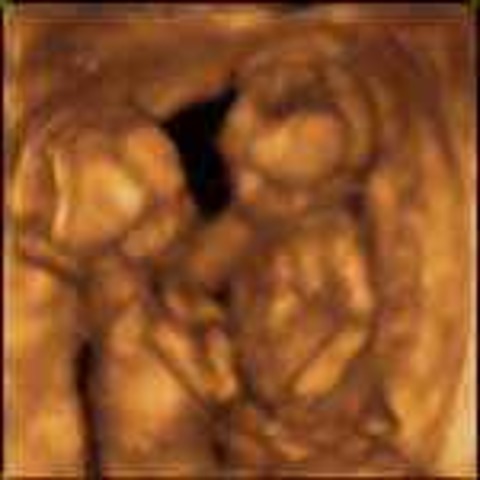

• Week 23

Week 23

Fetus can suck thumb with no problem. Inner ear helps with controling balance. Pancreas developes.